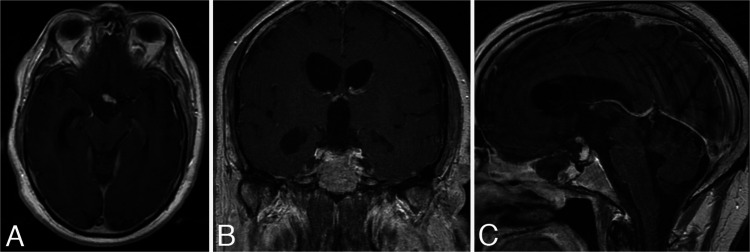

A 66-year-old male patient came to the emergency department displaying confusion and imbalance. He had a bitemporal hemianopsia on examination. Endocrine laboratory tests showed no apparent hormonal disturbances. His initial brain computed tomography scan showed a 2.1 × 1.9–cm heterogeneous mass in the sellar and suprasellar region that was exerting a mass effect upon the anterior third ventricle and causing obstructive hydrocephalus. Magnetic resonance imaging (MRI) showed a 3.8 × 2.1 × 2.4–cm, heterogeneously enhancing mass consistent with a pituitary macroadenoma (Fig. 1). The tumor contained hemorrhage and necrosis within the suprasellar component, and it had slight extension into the right cavernous sinus. Having the impression that the tumor was a pituitary macroadenoma, we completely removed it through an endoscopic transsphenoidal resection (Fig. 2). A vascularized nasoseptal flap and an abdominal fat graft were used to prevent postoperative cerebrospinal fluid leakage. Histopathological examination confirmed the diagnosis of an NPA (Fig. 3A). Immunohistochemical stains showed PA cells that were patchily positive for adrenocorticotropic hormone, whereas they were negative for prolactin, growth hormone, thyroid-stimulating hormone, luteinizing hormone, and follicle-stimulating hormone. The patient had an excellent recovery with normalization of his vision and mental status, although the hypopituitarism remained and was corrected with medication. He was followed up for four years, including serial MRI, but stopped coming for routine examinations after that point.

FIG. 2.

Postoperative MRI after initial surgery. Axial (A), coronal (B), and sagittal (C) contrast-enhanced T1-weighted images. Gross-total resection of the tumor was done. Ventricular size normalized on follow-up imaging.